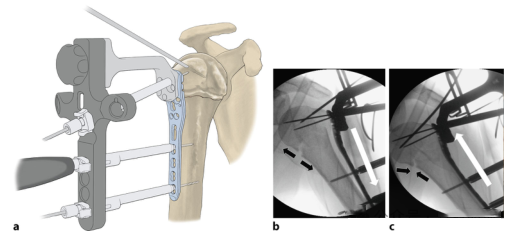

Плечо тянется продольно, а поскольку диафиз плечевой кости часто смещается в передне-медиальном направлении, в подмышечной впадине можно разместить дополнительную спираль (а) для облегчения репозиции (черная стрелка на b). При многофрагментарных переломах небольшой внешний поворот на 30° может сблизить смещенные дорсально фрагменты. Если адекватная репозиция невозможна, требуется прямая открытая репозиция. 3. Выбор кромки ножа